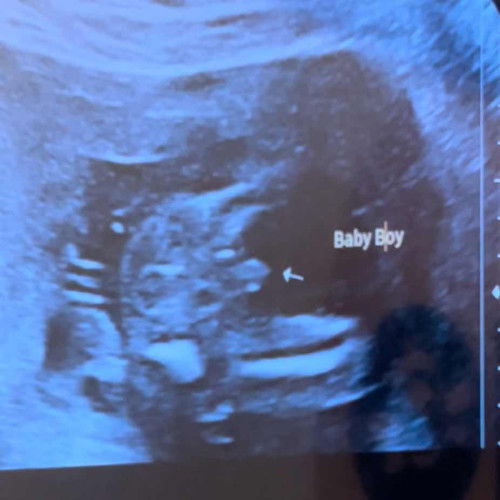

Scan gender 16 week

Tolong mommy yg ada anak boy , kalau scan tunjuk mcm ni mmg konfem boy ke 🥹 takut kena scam huhuhu sbb anak first dah girl , ini anak kedua , takut berharap pulak 😌 tapi dh dua kali scan dokter kata boy jugak . saya scan ni time 16week 3days , elok dia duduk terkangkang . sama ke bentuk mcm ni kalau boy ? #bantujawab #gender16weeks #dueapril 2026

Baca lagiMintak maaf sis bukan nak downkan sis tapi sedara saya 2 girl kandungan ketiga dr 20 week smp nak dekat bersalin doktor scan semua ckp boy dh excited brg semua beli boy punya sekali keluar girl rupanya yg nmpk mcm kemaluan dia tu sebenarnya tali pusat dia yg dia letak celah kankang , saya suggest sis buat scan 5d lebih accurate saya pn first baby haritu scan 5d terus tkt kena scam dengan baby kalau 5d tu mmg nmpk jelas kemaluan dia

saya scan pertama x nampak,scan kedua x tunjuk scan details masa 7 bulan baru nampak pistol. dan masa nak bersalin doktor tanya boy ke girl? baby marah terus memancut dan bagi tahu masa scan saya boy lah doktor. anak perempuan saya 3 orang semua nyorok. Alhamdulillah yang ini tunjuk masa sujud. saya tengok scan awak baby boy

semlm sy scn 5D+gender doc ckp klau boy mmg 13 mnggu dh bole npk..klau pmpn kdg sembunyi..biasa lelaki npk pistol..klau pmpn burger(terbelah)sis pnya scn Tu mmg terang boy sme ank sy cmtu lah bntuk.nye..tahniah sis..